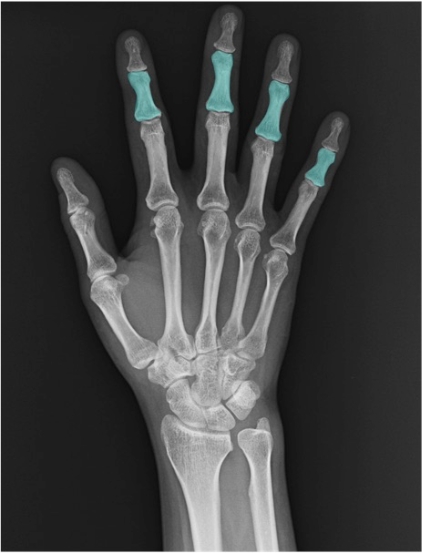

近位手根骨

三角骨(triquetrum)

尺側近位列に位置。PA正面像では豆状骨(pisiform)に重なりやすいため輪郭が不明瞭なことがあります。斜位像では輪郭把握が容易。

月状骨(lunate)

近位列中央。側面像で橈骨遠位端〜月状骨〜第3中手骨が一直線に配列するか確認(いわゆるアライメント)。半月形の輪郭と骨皮質の連続性に注目。

舟状骨(scaphoid)

近位列橈側。PA正面、尺屈位(ulnar deviation)で舟状骨の短縮・重なりを回避しやすく、腰部(waist)の評価がしやすくなります。